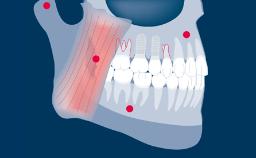

Design of all implant prostheses should be based on a prosthodontic plan and should address all specific planning factors identified as relevant.

There are a number of aspects that are common to the design of most implant fixed dental prostheses (or FDPs), and it is helpful to arrange these points in a logical design sequence.

The first point is selection of the type and configuration of the FDP. The next point is selection of the retention method, followed by consideration of the external aspects and internal structure required to address factors such as esthetics, function, and strength.